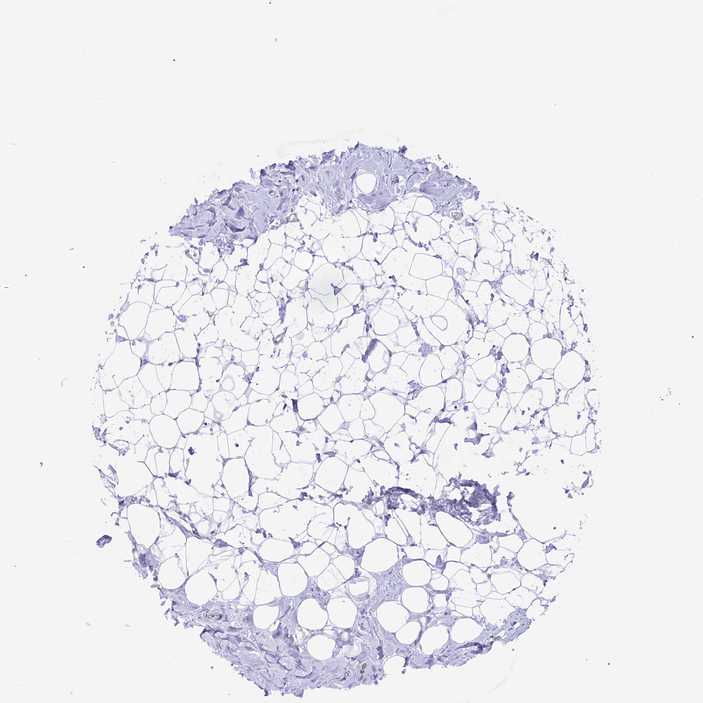

BREAST - Antibody stainingi

Antibody staining in the annotated cell types in the current human tissue is reported as not detected, low, medium, or high, based on conventional immunohistochemistry profiling in selected tissues. This score is based on the combination of the staining intensity and fraction of stained cells.

Each image is clickable and will lead to virtual microscopy that enables deeper exploration of all samples and also displays staining intensity scores, fraction scores and subcellular localization as well as patient and tissue information for each sample.

Antibody HPA042791

Adipocytes Not detected

Glandular cells High

Myoepithelial cells Not detected